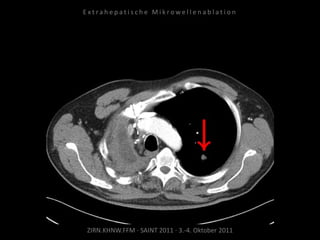

Ablation am 24.03.2010:

2 Nadelpositionen.

Kontrolle:

MRT 05.04.2010

Kein weiteres Wachstum.